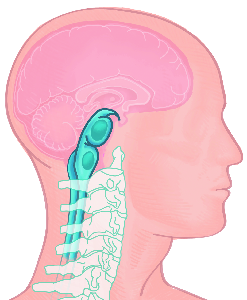

Detailreiche Fotografien aus der medizinischen Praxis ergänzen die Texte; moderne, genaue,

wissenschaftliche Zeichnungen geben Einblick in die Anatomie und die Funktion der Lunge und

anderer Organe.